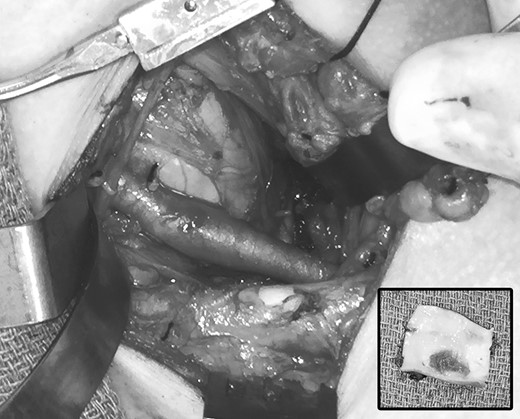

Clinical evaluation revealed an absence of palpable pulses at the left wrist but adequate arterial circulation to the hand at rest, with brisk capillary refill in the fingers and no signs of digital embolism. Upper extremity strength, sensation and range of motion were normal and there were no signs of swelling, edema or cyanosis to suggest venous obstruction. The patient was brought to the operating room for thoracic outlet decompression using a left supraclavicular approach. After mobilizing and rotating the scalene fat pad on a lateral pedicle, the phrenic nerve was identified in its expected position on the surface of the anterior scalene muscle; however, the subclavian artery was not found within the scalene triangle adjacent to the brachial plexus, but in front of the anterior scalene muscle insertion on the first rib, in the costoclavicular space directly posterior to the phrenic nerve (Figs 4 and 5). Thoracic outlet decompression was performed with anterior and middle scalenectomy, brachial plexus neurolysis and first rib resection [10]. Direct inspection and intraoperative left upper extremity arteriography demonstrated post-stenotic dilatation of the subclavian artery and chronic occlusion of the brachial artery with abundant collaterals. The affected segment of the subclavian artery was resected and found to contain an ulcerated lesion with thrombus (Fig. 6), and the artery was reconstructed with a 6-mm diameter cryopreserved femoral artery interposition graft (Fig. 7). The patient was discharged on postoperative Day 3 taking a direct oral anticoagulant and she was clinically stable during subsequent follow-up.

Operative photograph after thoracic outlet decompression, demonstrating area of post-stenotic dilatation in the left subclavian artery. Inset, excised segment of the affected left subclavian artery, demonstrating ulceration and thrombus on the luminal surface.